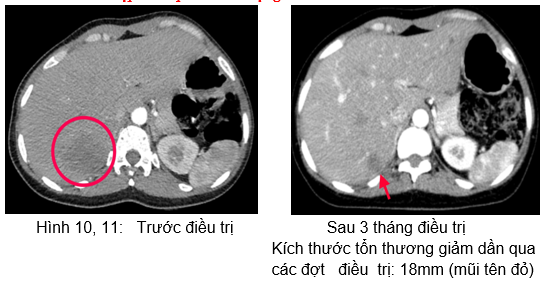

 Chụp cắt lớp vi tính ổ bụng:

Hình 12: Hình  ảnh CT ổ bụng sau 6 tháng điều trị: Khối nhu mô gan hạ phân thùy S7 giảm tỷ trọng, ngấm thuốc kém sau tiêm,

Kích thước tổn thương giảm dần qua  các đợt   điều  trị: và 15mm (mũi tên xanh).

Như vậy, bệnh nhân đáp ứng khá tốt với Erlotinib: chất chỉ điểm khối u, kích thước tổn thương phổi, tổn thương gan có xu hướng giảm dần.